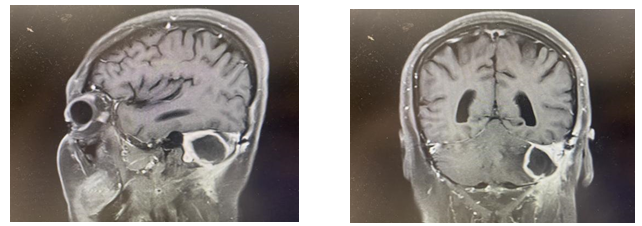

圖:核磁提示腦膿腫形成

術(shù)后1個月(2024-2-27)患者無明顯誘因出現(xiàn)頭暈,有四肢感覺麻木,患者于天壇醫(yī)院復(fù)診,行核磁檢查,考慮腦膿腫。急診予以萬古霉素+美羅培南+地塞米松+甘露醇治療1天后狀態(tài)明顯好轉(zhuǎn)。